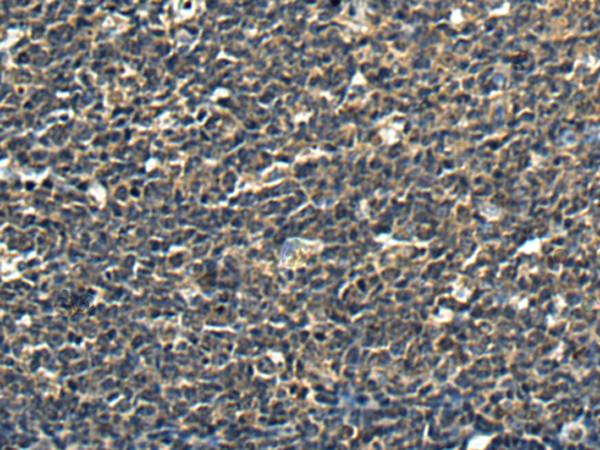

IHC positive control: |

Human tonsil |